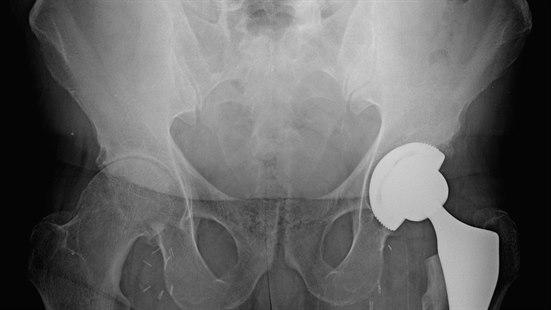

Lårhalsbrudd er blant de 10 hyppigste årsaker til uførhet blant voksne. For eldre og skrøpelige pasienter er et lårhalsbrudd en alvorlig skade forbundet med økt morbiditet og mortalitet1. Historisk sett har de fleste lårhalsbrudd blitt behandlet med intern fiksasjon, mens dagens retningslinjer anbefaler artroplastikk for disloserte lårhalsbrudd for eldre pasienter. Flere systematiske oversikter har rapportert at total hofteartroplastikk (helprotese) er bedre enn hemiartroplastikk (halvprotese) hos friske, oppegående pasienter, men det er bekymring for at en total hofteartroplastikk medfører et større kirurgisk traume og høyere potensiell risiko for senere dislokasjon2.

Dette er bakgrunnen for en studie publisert i New England Journal of Medicine, HEALTH-studien3. 1495 pasienter som var 50 år eller eldre og som hadde et dislokert lårhalsbrudd, ble randomisert til enten total hofteartroplastikk eller hemiartroplastikk. Alle de inkluderte pasientene hadde vært oppegående og selvhjulpne før bruddet oppstod. Studien ble gjennomført ved 80 ulike sentre i 10 land. Det primære endepunktet var en sekundær hofteoperasjon innen 24 måneder. Sekundære endepunkter var død, alvorlige bvirkninger, hofterelaterte komplikasjoner, helserelatert livskvalitet, funksjon.